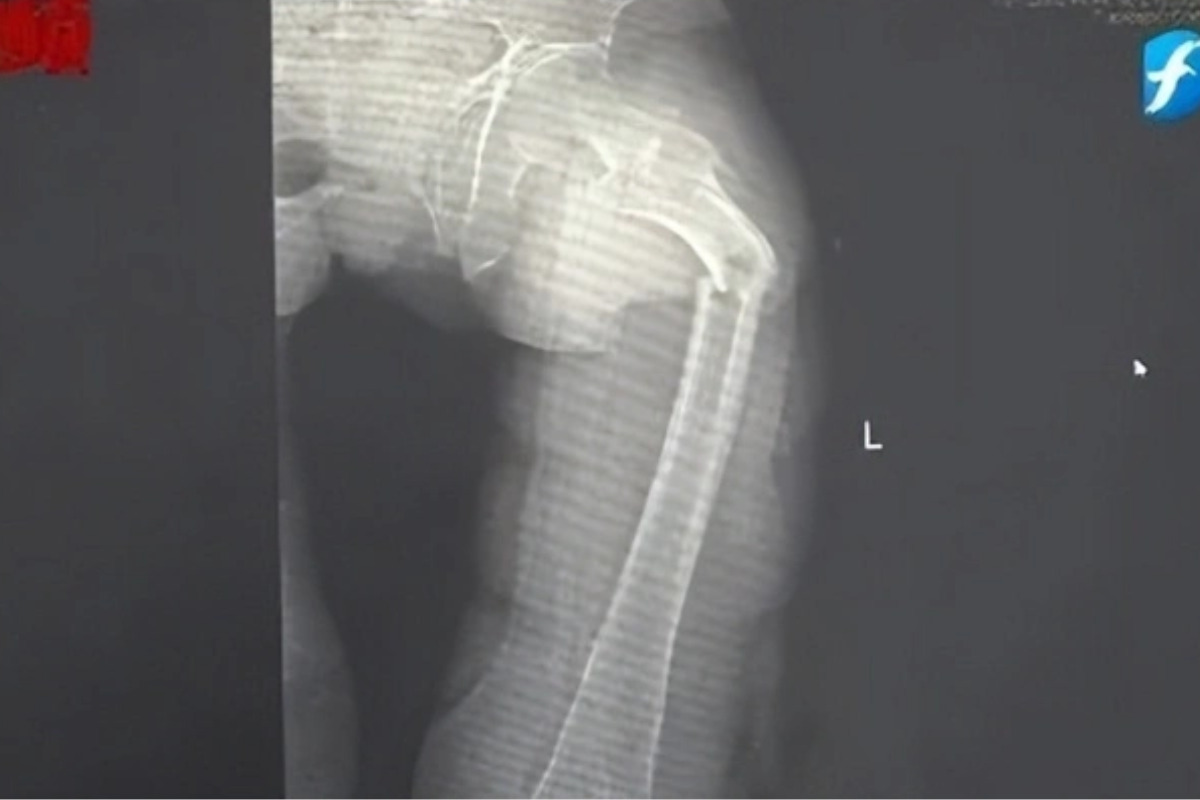

Đến nửa đêm, anh Cung bị giật mình tỉnh giấc vì cơn đau ở đùi. Anh phát hiện ra mình không thể đi lại được nhưng cố chờ đến trời sáng hẳn rồi nhờ người nhà đưa đi bệnh viện. Kết quả chụp X-quang tại Bệnh viện Nhân dân số 2 Phúc Kiến (Trung Quốc) khiến anh Cung sốc nặng: xương đùi trái của anh bị gãy làm hai mảnh.

Hình ảnh xương đùi bị gãy đôi vì loãng xương sớm của anh Cung Nguyên nhân uống nhiều nước ngọt có ga gây loãng xương được bác sĩ Đông Trung giải thích như sau: "Nước ngọt có ga chứa nhiều photpho và đường. Khi uống quá nhiều, cơ thể sẽ bị mất cân bằng canxi do photpho cản trở sự hấp thụ canxi. Hơn nữa, trong quá trình chuyển hóa đường, cơ thể phải tiêu thụ một lượng lớn khoáng chất quan trọng, bao gồm cả canxi. Điều này buộc xương phải giải phóng canxi để bù đắp, dẫn đến loãng xương và gãy xương".